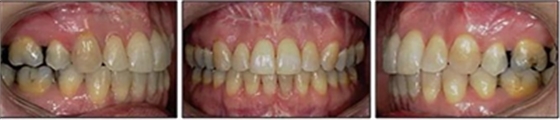

患者曾行正畸治療,現(xiàn)覺笑容不美觀前來就診。患者正面觀及側(cè)貌示下頜發(fā)育不足,偏高角,唇閉合不全。上下頜中線齊。覆合、覆蓋4毫米。磨牙關(guān)系及尖牙關(guān)系II類。上頜擁擠度4mm,下頜擁擠度6mm。4顆第一前磨牙在第一次正畸治療時已拔除。上下牙弓呈尖圓型,牙弓狹窄。

患者側(cè)貌改善,下唇唇肌緊張消失,上下唇可自然閉合。磨牙及尖牙關(guān)系糾正至I類,覆合覆蓋正常。上下頜弓型糾正至卵圓形,牙弓寬度增加。頭影測量分析示SNA角81.8°,ANB角3°。頭影測量重疊圖示下頜骨向后旋轉(zhuǎn),垂直面高度略有增加。